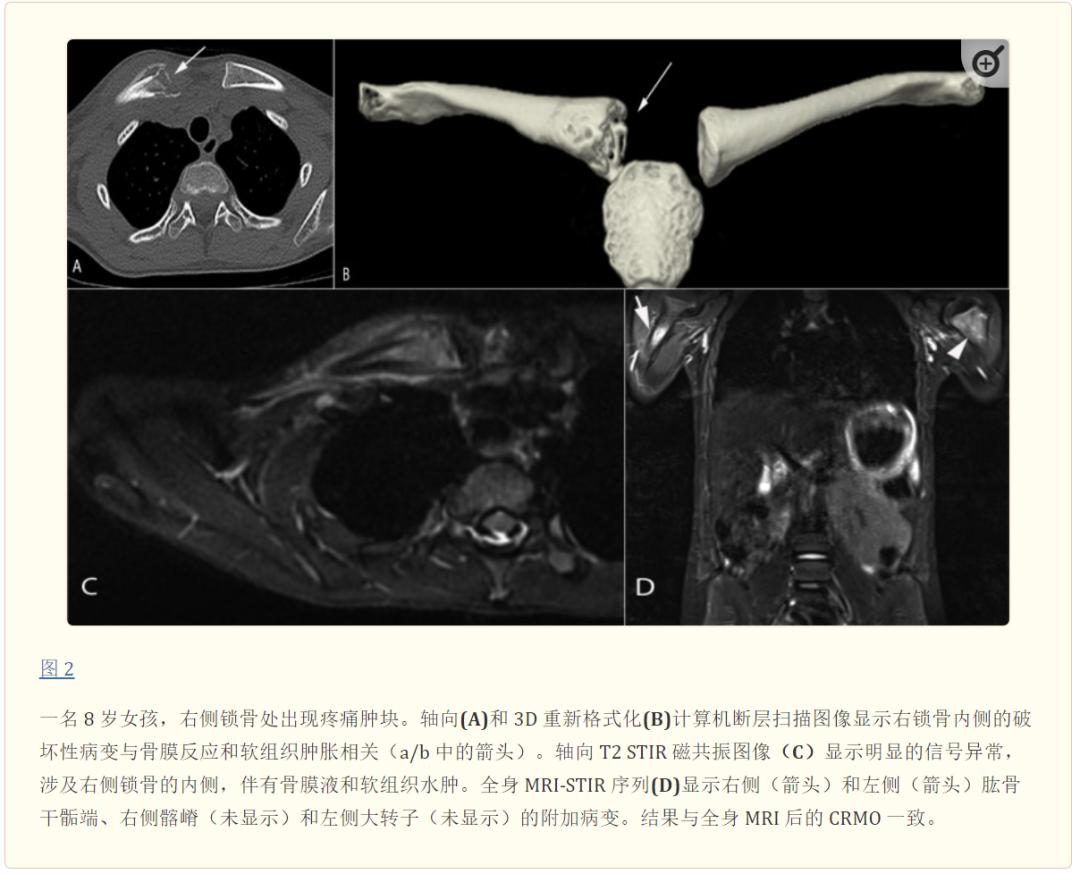

骨闪烁扫描已被全身磁共振成像 (MRI) 取代,以评估多灶性和受累程度、软组织受累并排除其他诊断。 最典型的发现包括骨髓水肿(T2 加权 MRI 图像上的信号增加,而T1 加权 MRI 图像上的信号减少),并以增强和骨膜炎/骨膜反应为特征。图 1,2。常伴有广泛的软组织水肿和炎症,关节受累有时会在 MRI 上出现滑膜炎迹象。

使用全身 MRI 描述了三种模式:(1)胫骨-阑尾多灶性模式,胫骨病变,多灶性且无锁骨受累(图1),(2) 锁骨-脊髓少灶性模式:锁骨病变和其他少数以脊柱为主的病变,无胫骨受累(图 2),和 (3) 胫骨-锁骨交叉模式。长骨干骺端,尤其是锁骨(CRMO 的经典部位)和下肢(股骨远端、近端、胫骨远端和腓骨远端)最常受累,如果累及孤立部位,最常见的是锁骨或下颌骨,这是极其罕见的。